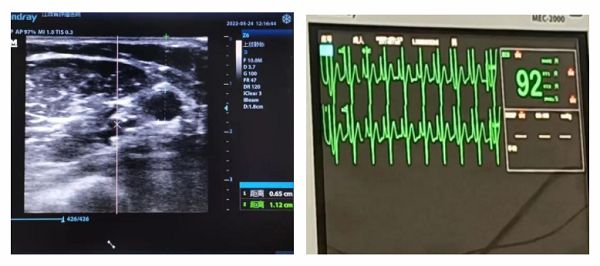

近日,万载县人民医院肿瘤科顺利完成县内首例 B 超引导下 PICC 置管术一一超导下外周中心静脉置管术,实现县域护理业务技能上的又一突破。

患者丁女士,今年56岁,卵巢癌术后3年复发一年余,为行化疗入住我科(肿瘤内科)。为了保护静脉,避免药物外渗,顺利完成化疗周期,经肿瘤科护士长姚志英带领的 PICC 小组充分评估后,拟经右侧上臂贵要静脉行 PICC 置管术,8月8日,姚志英护士长及专科护士龙灵在超声引导下成功完成首例B超引导下 PICC 置管。术中出血少、患者疼痛感较轻,导管尖端位于上腔静脉,无置管并发症发生。置管成功后,患者及家属表示非常满意。

超声引导下应用改良塞丁格技术行 PICC 置管是目前临床上 PICC 置管的“黄金标准”,通过超声引导的帮助确定位置,深度以及穿刺部位,可置管显示血管解剖结构,全程可见、损伤小、定位准、大大提高了一次性穿刺的成功率、对于临床中常见的肥胖、水肿、反复化疗、静脉血管条件极差的患者,应用B超引导下 PICC 置管术可解决这些难题。以往血管条件差的患者都要到宜春、南昌才能完成,现在超声引导下 PICC 置管在县域内开展,节约了患者的就诊时间,减少了患者的经济负担。